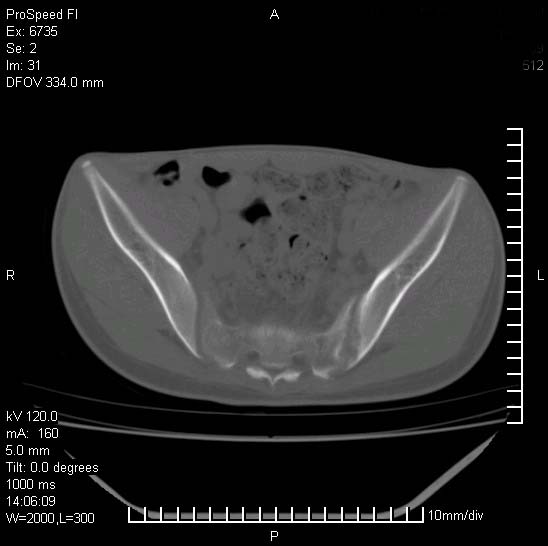

患者自诉胯部疼痛两年余,在当地服用中药,半月前至本院考虑骶髂关节结核,给予抗痨治疗。现发展至右下肢疼痛明显,活动受限,以膝关节处明显,拍膝关节平片无明显异常。

两侧骶骼关节改变,考虑强直性脊炎

左侧骶髂关节面限局性骨破坏,边缘硬化关节腔见钙化物;不出外tb

右侧骶髂关节也有类似改变,只是较左侧轻,首先考虑强直性脊柱炎,不除外结核,建议作hla-b27检查。

典型强脊炎改变,髋关节亦有累及

符合强直性脊柱炎表现。